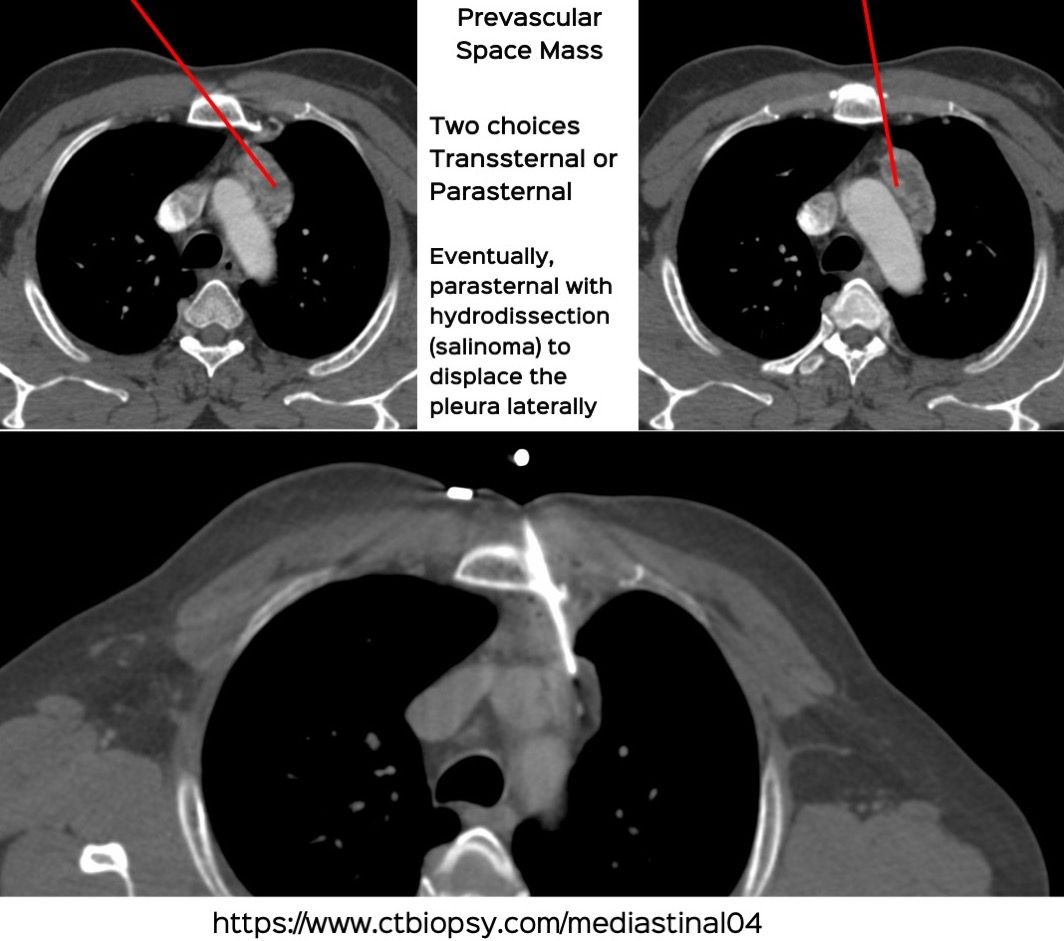

Case 77: Prevascular Space Mediastinal Mass Biopsy Using a Parasternal Approach with Hydrodissection (Salinoma)